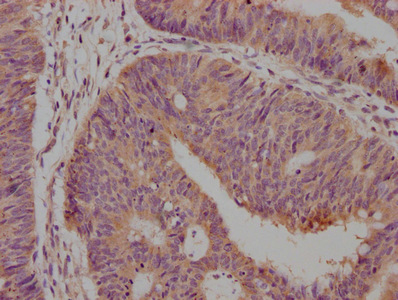

IHC image of CSB-MA004950A1m diluted at 1:500 and staining in paraffin-embedded human lung cancer tissue performed on a Leica BondTM system. After dewaxing and hydration, antigen retrieval was mediated by high pressure in a citrate buffer (pH 6.0). Section was blocked with 10% normal goat serum 30min at 37°C. Then primary antibody (1% BSA) was incubated at 4°C overnight. The primary is detected by a Goat anti-rabbit IgG labeled by HRP and visualized using 0.05% DAB.

-